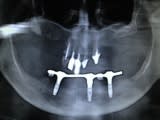

reprise d'une barre all on five:

au départ all on five réalisé par un confrère, à l'arrivée all on three après per de 2 implants !

repris en basale avec 2 plaques et un axial supplémentaire